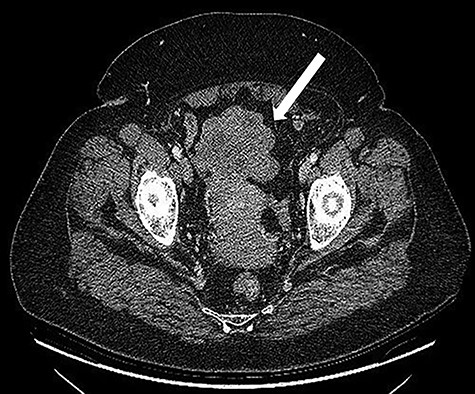

A 68-years-old woman (body mass index 35.6) was admitted with recent onset sideropenic anemia and not heart-related angina pectoris. At physical examination, a slightly mobile mass in the left iliac fossa was palpable. Carcinoembryonic antigen, carbohydrate antigen 19.9 (CA 19.9) carcinoma antigen 125 (CA 125) were normal. Upper and lower GI endoscopy were negative for any lesion. The patient was submitted for computed tomography (CT) scan, showing multiple solid density processes with colliquation areas in the abdominal cavity (Fig. 1). The greatest mass (8.0 × 5.6 cm) was located in the pelvis in close contact with the uterine fundus and the small bowel (Fig. 2). Cranially to this process, at least 20 other tumors with a diameter between 0.8 and 3.8 cm could be appreciated.

CT scan: Bulky (8.0 × 6.5 cm) mass located in the pelvis in close contact with the uterine fundus.